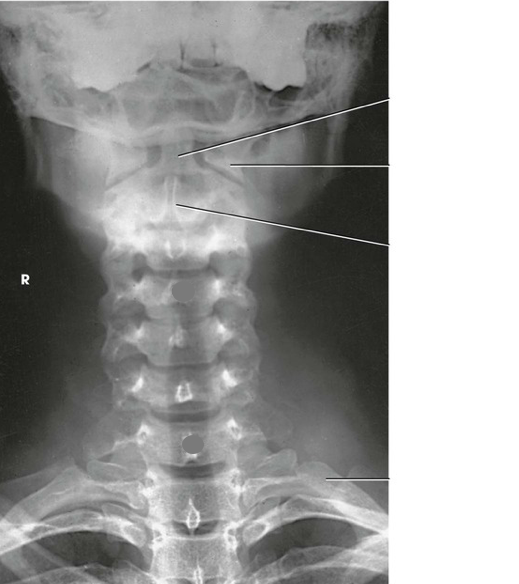

Question 2

Question

Label the image

Image:

Answer

C4

occipital bone

intervertebral disk space

spinous process

C7